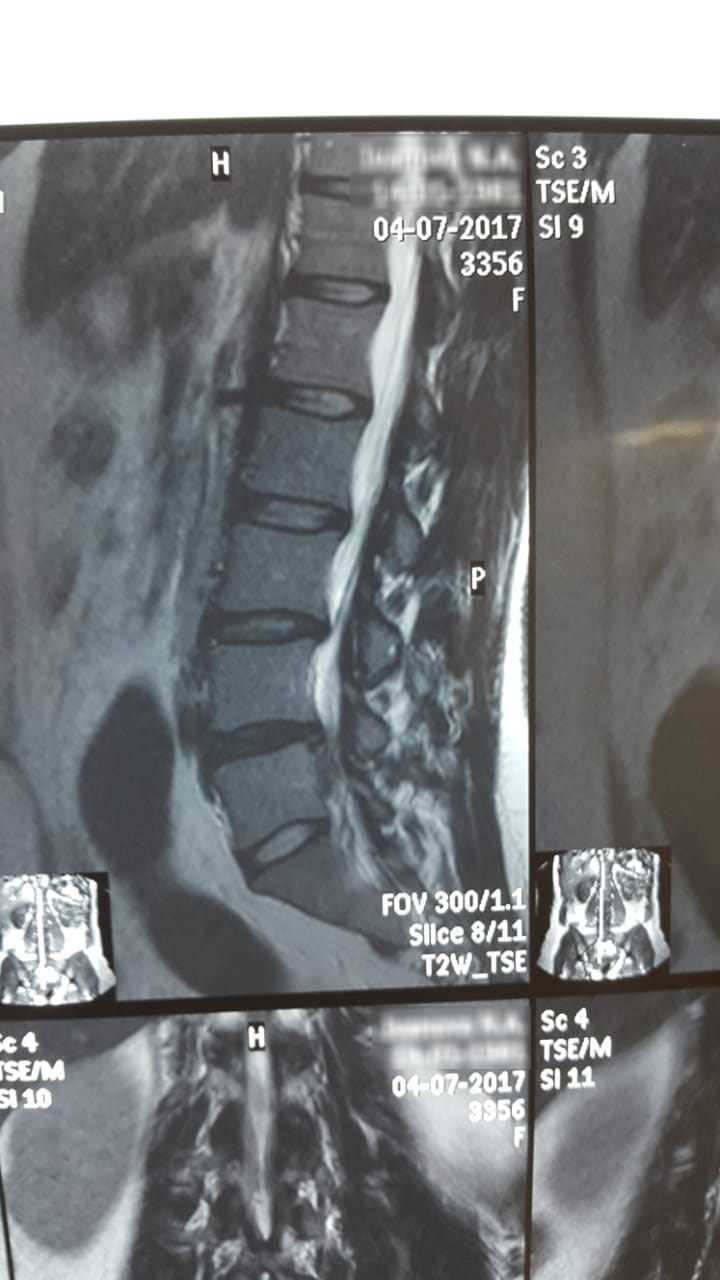

Грыжа — это состояние, при котором внутренние органы или ткани выходят за пределы своей обычно положенной позиции, часто через слабое место в мышечном или соединительном слое. Это может вызывать болевые ощущения, дискомфорт и ограничивать физическую активность. Люди с грыжей могут столкнуться с ограничениями при выполнении повседневных задач, таких как поднятие тяжестей или активные занятия спортом. Однако, многие из тех, кто столкнулся с подобной проблемой, смогли адаптироваться и продолжить вести полноценную жизнь, используя различные методы лечения и реабилитации.

Каковы основные методы лечения грыжи и каковы истории вдохновения людей, которые прошли через этот процесс?

Основные методы лечения грыжи включают консервативные подходы, такие как физическая терапия и изменение образа жизни, а также хирургическое вмешательство, которое может быть необходимым в более серьезных случаях. Истории вдохновения можно встретить среди людей, которые, несмотря на диагноз, не опустили руки. Например, один из пациентов начал заниматься плаванием после операции, что не только укрепило его физическое здоровье, но и дало возможность участвовать в соревнованиях. Другие вернулись к занятиям спортом и активному образу жизни, что показало им, что грыжа не должна становиться препятствием на пути к мечтам.